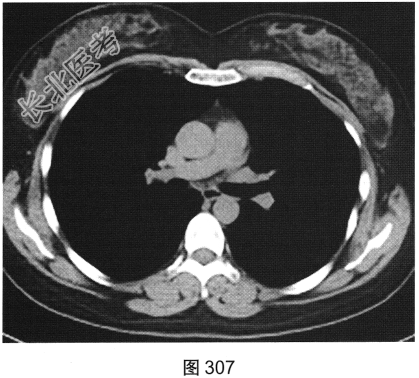

- [材料题] 患者女性,32岁,因“间断刺激性干咳1年,发现肺部囊性病变8个月”就诊。患者无发热、咯血、胸痛、呼吸困难。服甘草片、阿莫西林无明显好转。胸部HRCT如图302~图307所示。

- 多项选择题2.影像检查所示肺内主要病变的形态、分布特点为( )

C、囊状透亮影形状规则,大小及肺内分布均匀

G、囊壁较薄、略欠均匀,部分囊壁欠连续

- 多项选择题4.[提示]患者有长期吸烟史,已戒烟1年; 血ESR、CRP(一),血嗜酸性粒细胞(一), 血免疫球蛋白、免疫固定电泳及VEGF-D(一),ANA、ANCA(一); 抗dsDNA(一);腹部超声未见明显异常; 肺通气功能正常。给予拜复乐抗感染、沐舒坦化痰等对症治疗,咳嗽症状略缓解。结合患者临床及CT表现, 首先考虑诊断为( )

A、肺淋巴管平滑肌瘤病

B、肺朗格罕细胞组织细胞增生症